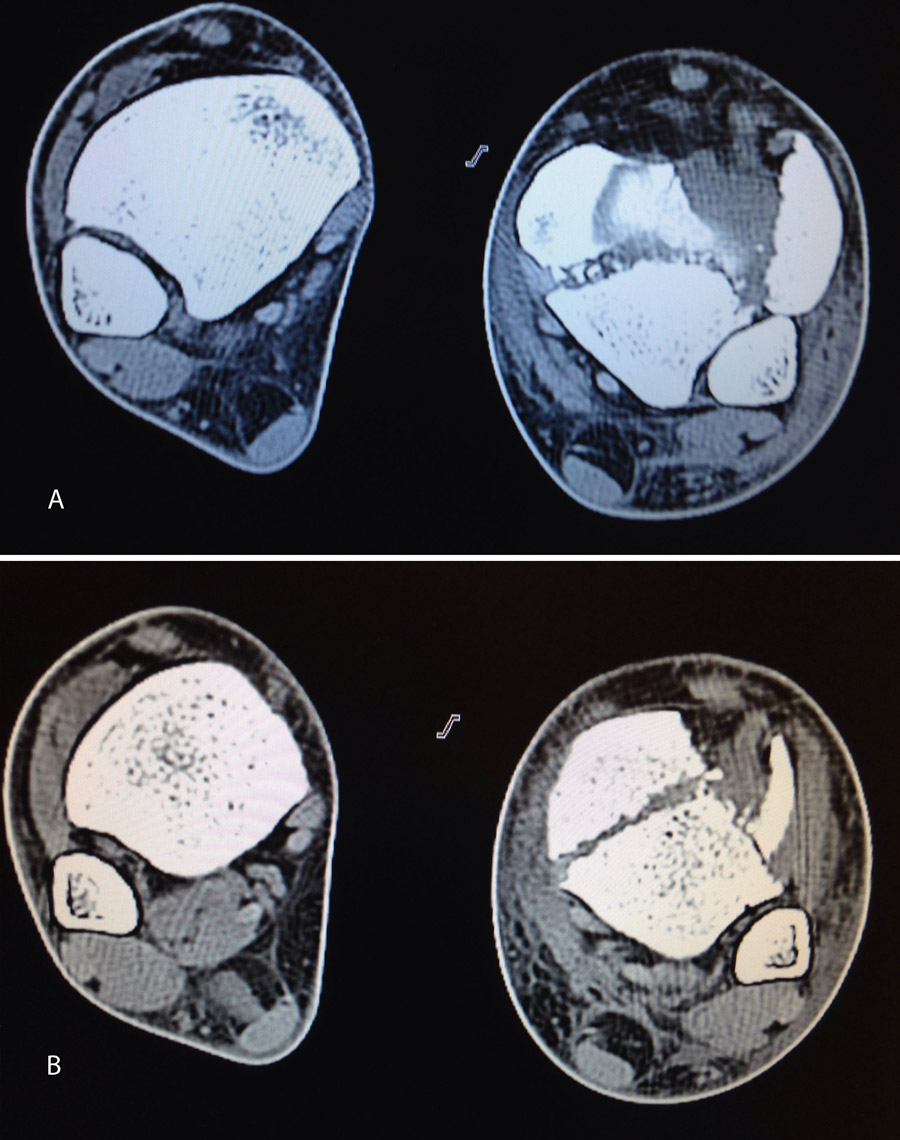

Figura 18. La tomografía computarizada muestra los fragmentos principales de la fractura, estando desplazado el Tillaux que se reduce con la tracción.

En este caso, es esencial observar las Rx con y sin tracción que nos indican cómo se va a comportar la fractura. Si la fractura es reductible en tracción, es muy probable que podamos realizar una osteosíntesis con restitución completa de la superficie articular. Al realizar la TC, apreciamos la disposición de los fragmentos para marcar una estrategia de reducción bajo control radioscópico y artroscópico, y colocación de los tornillos canulados que fijarán la epífisis distal de la tibia.